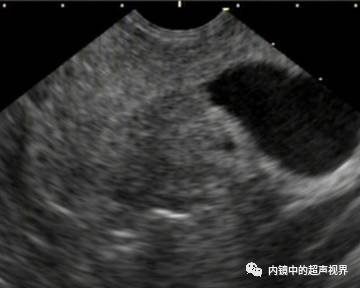

我现在使用的超声内镜DR可调节范围为30-90。以下三张图片显示的是同一个胰头肿物,肿物回声与胰腺回声非常接近,DR分别为90、70、40,其它参数相同,您更喜欢哪一张。

胰头占位